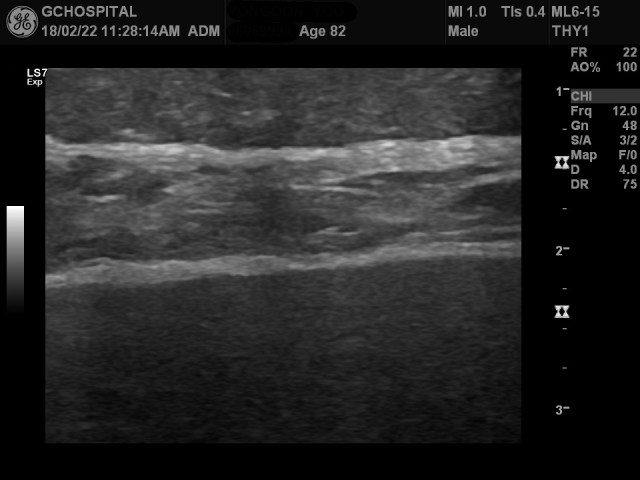

위는 12MHz frequency linear probe를 통해 간 좌엽을 스캔한 영상입니다. 일견 보기에는 간표면이 매끄럽고, 별다른 문제가 없어보입니다.

하지만, 이를 좀더 확대해보면, 간 피막의 윤곽이 울퉁불퉁하게 요철이 보이고, 왼쪽 영역에선 focal nodularity도 확인할 수 있습니다.